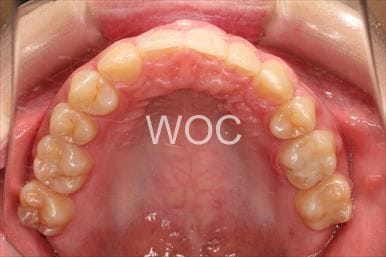

治療後1

治療後2

治療後3

治療後4

治療後5